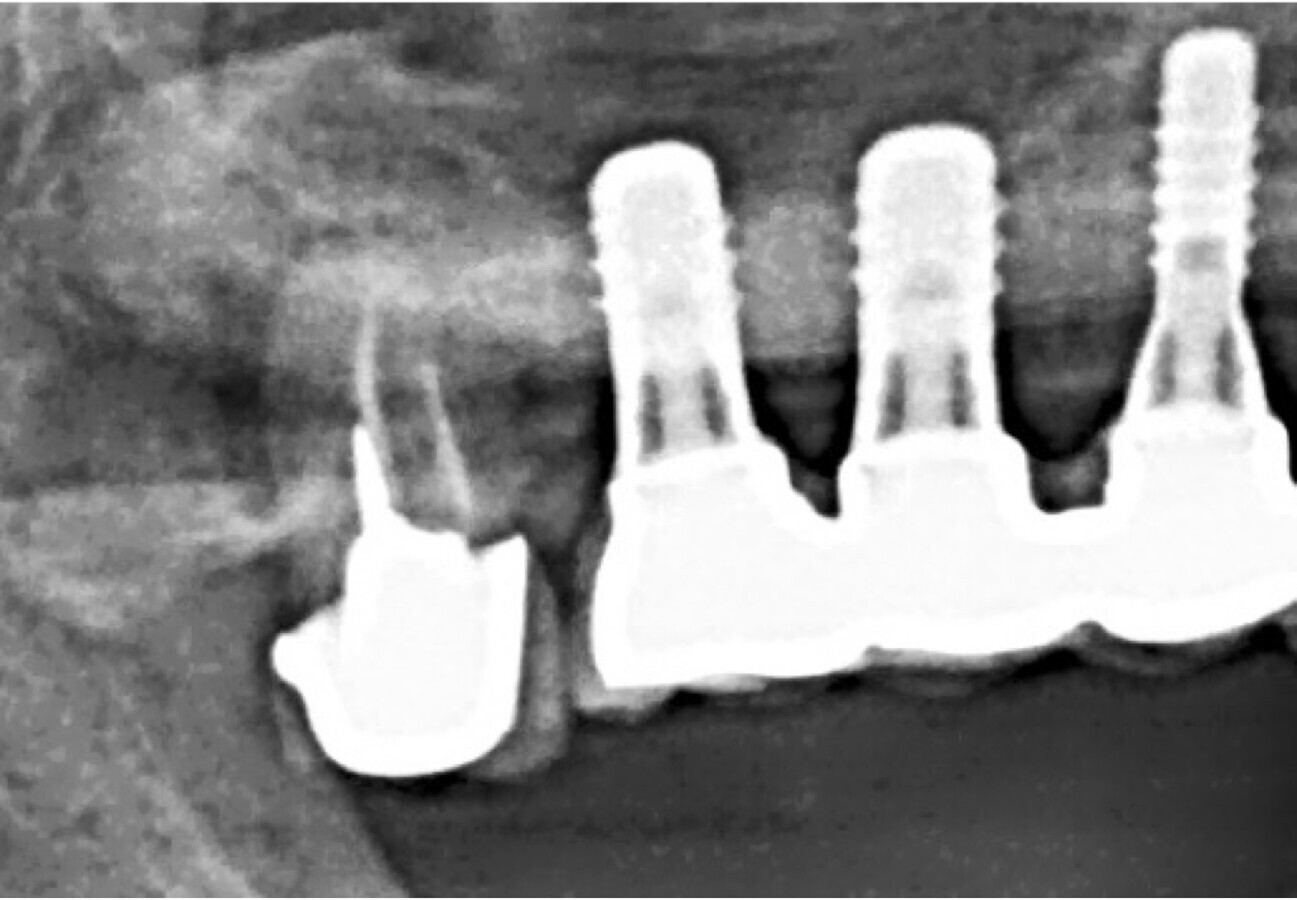

Figura 1.Colocación de implantes en el maxilar superior de un paciente 79 años con deficiencia vitamina D. Se comienza tratamiento prequirúrgico con vitamina D de 0266 mg cada 7 días por 3 meses en este caso clínico realizado por Dr. Iván Herrera Ustariz.

Figura 5. En este control radiográfico a los 3 meses se observa la adaptación de los implantes.